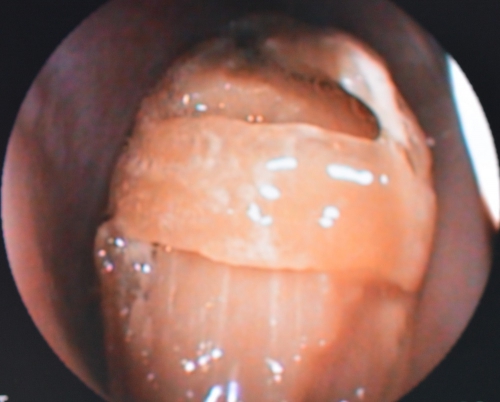

レントゲン検査などで明らかになった異物に対して、できるだけ速やかに内視鏡検査を実施いたします。内視鏡(左下写真)を用いて異物がどのように食道を閉塞をしているのか、その素材や形を評価して最適な除去方法を判断します。

内視鏡検査の結果、異物が消化可能なもので食道内を移動できるのであれば、内視鏡を用いて速やかに胃内に落とすことが基本的な対処法です。頚部食道の上流にある異物や「胃で消化できないもの」、胸部食道に損傷を与える恐れのあるものであれば、直接食道を切開して摘出したり、内視鏡下で様々な異物摘出鉗子(右下写真)などを用いてそのまま口から取り出することもあります。